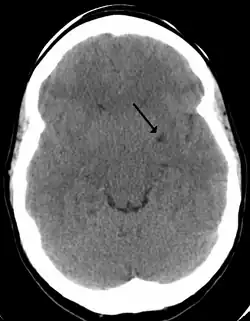

A perivascular space as seen on CT

CT image showing extensive low attenuation in the right hemispheric white matter due to dilated Type 2 perivascular spaces